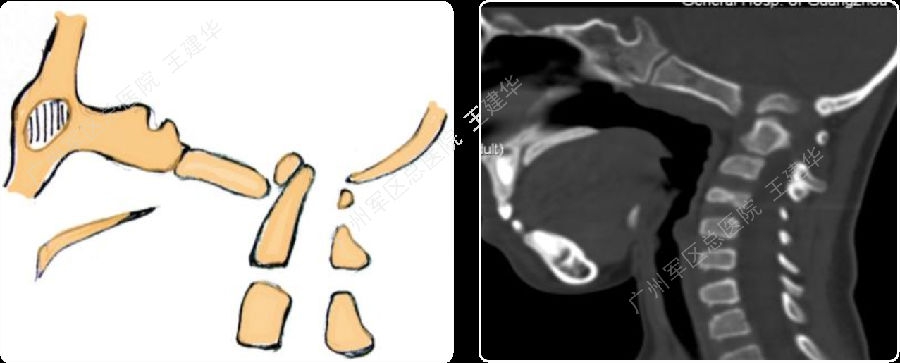

病例5

我院复查的颈椎MR及X片

如何手术?

本例患者手术过程

术前术后对比